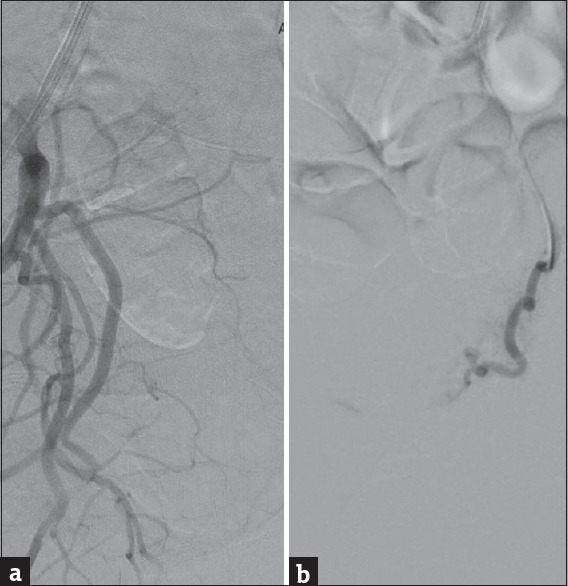

Cervical ectopic pregnancy (CEP) is a rare and challenging condition that requires prompt management to prevent complications. We present a case of a 27-year-old woman with a history of prior uterine surgeries who presented with vaginal spotting. Ultrasonography revealed an empty uterine cavity and a growing gestational sac with a viable foetus in the cervical canal. Despite methotrexate therapy, her beta-human chorionic gonadotropin hCG levels continued to rise, necessitating an alternative treatment approach. Bilateral uterine artery embolisation (UAE) was performed to reduce the risk of haemorrhage before hysteroscopic resection of the pregnancy. The combined approach of UAE and hysteroscopic resection successfully managed the CEP, leading to a favourable outcome. This case highlights the importance of early detection, tailored interventions and multidisciplinary collaboration in the management of CEP. UAE, in conjunction with hysteroscopic resection, offers a promising treatment option for CEP, minimising complications and preserving reproductive health.